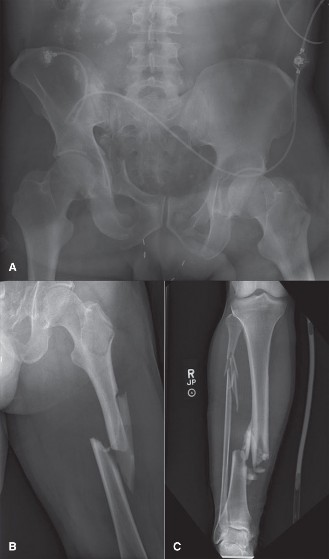

2. الفحوصات التصويرية السريعة

للحصول على صورة شاملة للإصابات، يتم إجراء فحوصات تصويرية سريعة:

*

الفحص الشامل (Pan-Scan CT):

غالبًا ما يتم إجراء فحص مقطعي محوسب (CT) شامل للرأس والعمود الفقري العنقي والصدر والبطن والحوض فورًا في قسم الطوارئ. هذا يوفر معلومات حيوية حول الإصابات الداخلية والكسور الرئيسية.

*

الأشعة السينية التقليدية:

يمكن إجراء أشعة سينية بسيطة للأطراف المشتبه في إصابتها لتقييم الكسور.

*

تصوير الأوعية الدموية (Angiography):

قد يكون ضروريًا في حالات الشك في إصابات الأوعية الدموية في الحوض أو الأطراف.

- التصوير: غالبًا ما يتم إجراء فحص شامل (CT للرأس، العمود الفقري العنقي، الصدر، البطن، الحوض) عند الوصول إلى قسم الطوارئ لتحديد الإصابات الأولية. الأشعة السينية البسيطة لإصابات الأطراف المشتبه بها عادة ما تكون كافية لتخطيط DCO. قد يكون تصوير الأوعية الدموية ضروريًا لإصابات الحوض أو الأوعية الدموية في الأطراف.